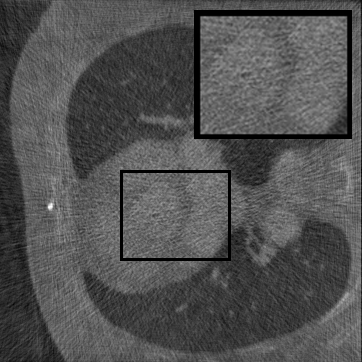

Figure 3: Visual comparison on TomoBank and LoDoPaB under random masking (ratio = 0.8). Rows 1 and 3 show the inpainted sinograms, while Rows 2 and 4 present the corresponding FBP (Ramachandran and Lakshminarayanan, 1971)-reconstructed images.

Table 1 summarizes the quantitative performance of FCDM and all baselines on the TomoBank and LoDoPaB datasets under both random and periodic masks. Figure 3 presents qualitative comparisons at a mask ratio of 0.8, showing both the inpainted sinograms and the reconstructed images obtained using FBP (Ramachandran and Lakshminarayanan, 1971). Across all settings, FCDM consistently achieves the highest SSIM and PSNR values, demonstrating its strong capability in recovering structural details and suppressing noise-induced artifacts. Visual results in Figure 3 further confirm that FCDM produces smoother and more consistent sinograms, while other methods often exhibit angular streaking or local inconsistencies.